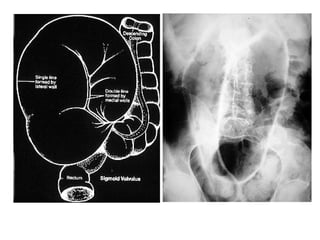

TAÉC RUOÄT

*Daáu hieäu: daõn, tröôùng hôi vaø dòch

1. Ruoät non > 3cm

2. Ruoät giaø > 6cm, manh traøng > 8cm

3. Möïc nöôùc – hôi ( xuaát hieän töø 12-24giôø)

4. Thaønh ruoät phuø neà ( >3mm)

5. OÅ buïng môø (dòch trong oå buïng)

 Phaân loaïi

1. Theo vò trí: ruoät non, ruoät giaø

2. Theo nguyeân nhaân: taéc ruoät cô naêng , taéc ruoät

cô hoïc.

- Taéc ruoät cô naêng : lieät ruoät

- Taéc ruoät cô hoïc : taéc ruoät do bít, do thaét

Phaân bieät möùc nöôùc hôi trong:

1. Taéc ruoät non:

- Naèm ôû trung taâm: hoá chaäu (P)  haï söôøn (T)

- Chieàu roäng > chieàu cao

- Caùc neáp maûnh, naèm gaàn nhau

- Nhieàu quai ruoät, kích thöôùc nhoû

2. Taéc ruoät giaø:

- Naèm ôû ngoaïi vi

- Chieàu cao > chieàu roäng

- Caùc neáp daøy, ít

- Vaøi quai ruoät voùi kích thöôùc lôùn

- Veà sau keøm theâm taéc ruoät non